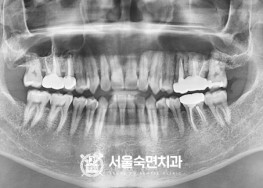

임플란트-치료-전후사진